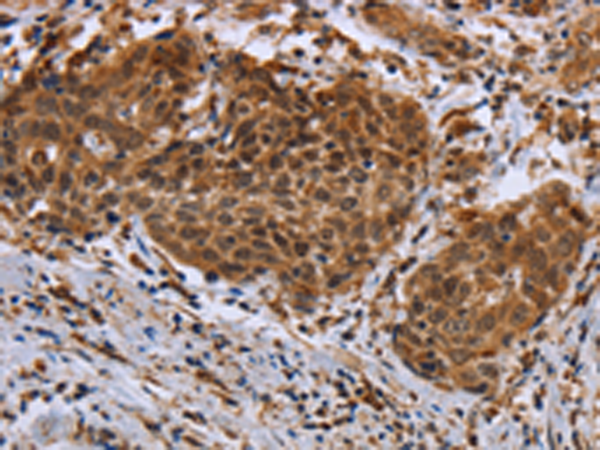

分类: 科研抗体货号: P10853别名: ALXR, HM63, FMLPX, FPR2A, FPRH1, FPRH2, FPRL1, LXA4R, FMLP-R-II应用: IHC反应种属: Human